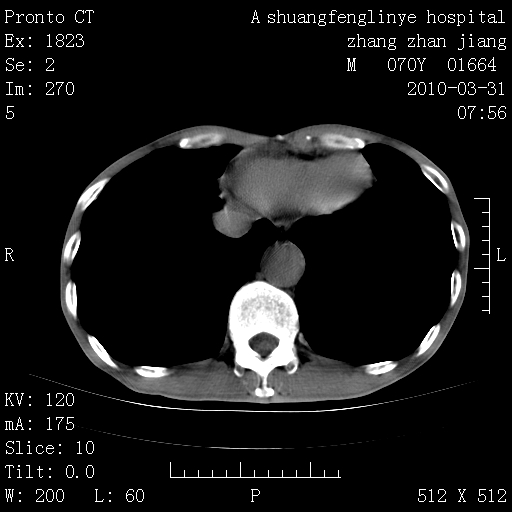

双上肺继发型tb并左上空洞形成,主动脉冠脉钙化。

支持:继发性肺结核伴空洞形成!建议纤支镜检查待出外周围型肺癌可能!

1)两肺上叶继发性肺结核并左肺上叶空洞形成。2)冠状动脉及主动脉钙化。